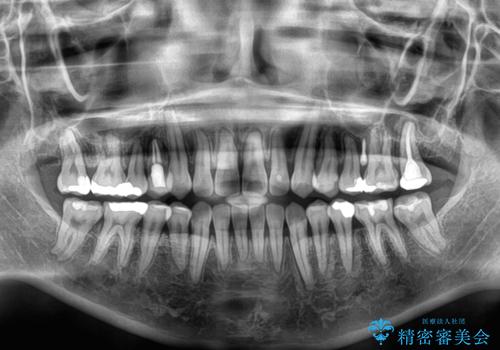

開咬をワイヤー装置で矯正治療

- 上下前歯が非接触となっている咬み合わせを気にして来院された患者様です。

開咬となっている原因の大半は、舌の突出癖によるものであるため、治療開始前から舌のトレーニングを開始し、スムーズに治療が進むようにしました。

開咬の方は、インビザライン矯正治療が適していますが、自己管理の煩わしさと、転勤の可能性がありマウスピース矯正であると通院しなくなるだろうとのことで、ワイヤー装置にて矯正治療を行うこととしました。

治療開始から8ヶ月ほどで遠方への転勤が決まりましたが、歯列は概ね整っていたため、その後は東京出張を狙って治療を終える処置を行うことができました。